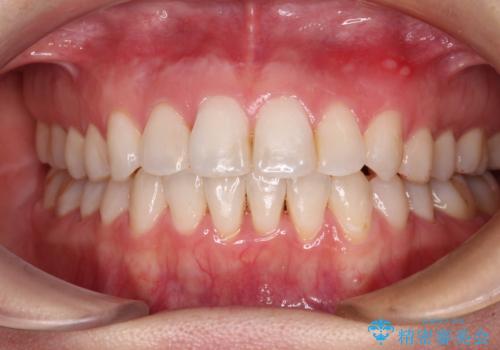

前歯のクロスバイト 目立たないワイヤー装置で矯正治療

- 2年2ヶ月

舌の突出癖の影響か、下顎前歯がなかなか整わず、治療期間は予定よりも長期間となりました。

舌突出癖改善のトレーニングの重要性を認識することとなりました。